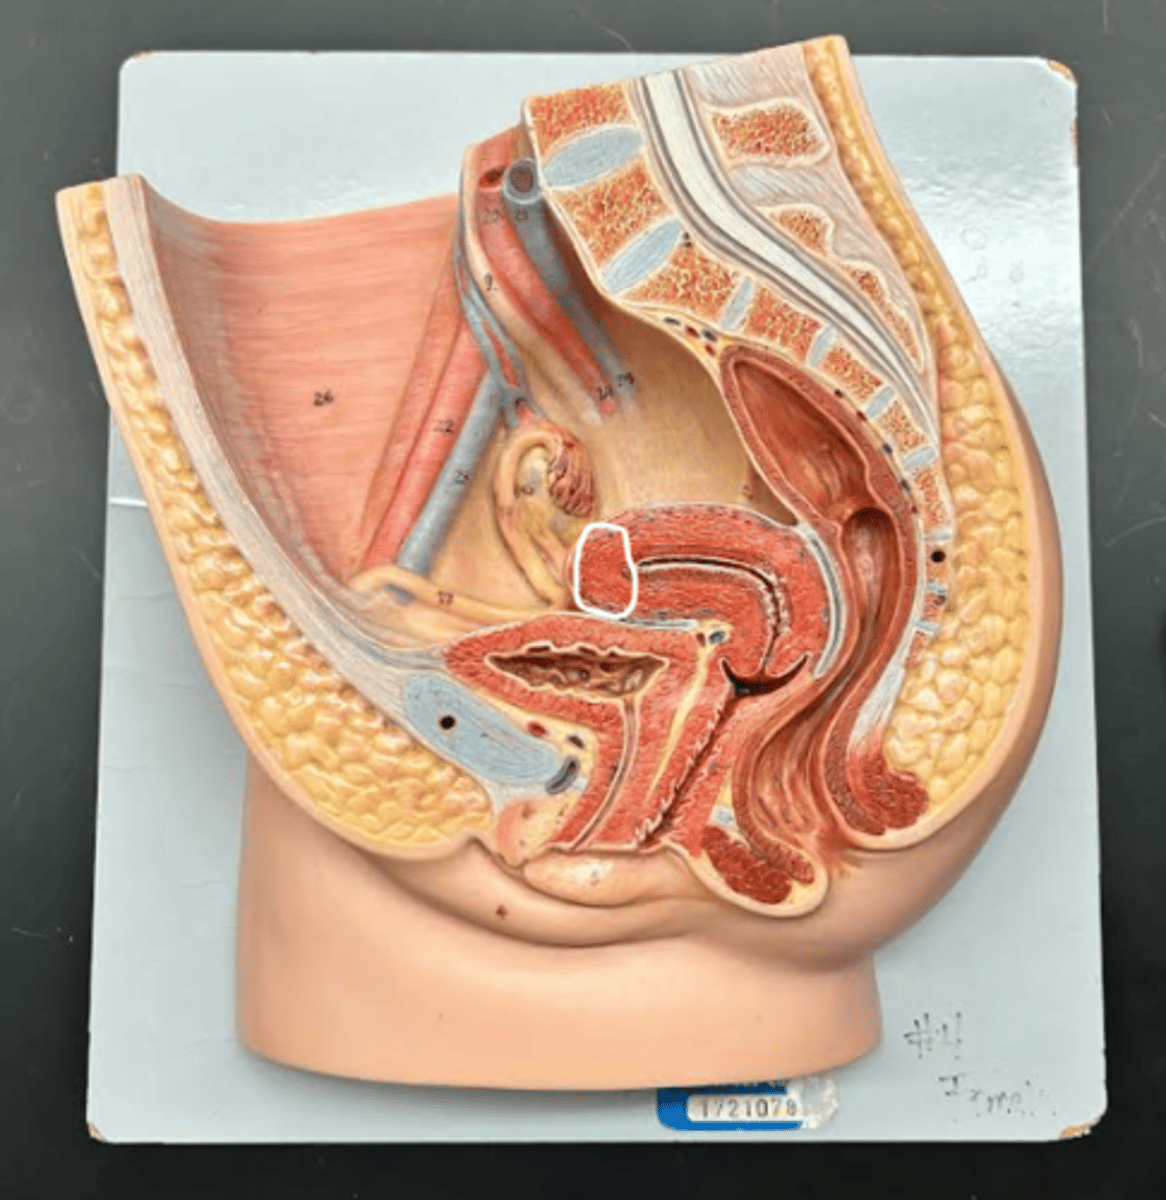

Chapter 29 Anat Phys: Female Reproductive System

Vagina

Vaginal orifice

Hymen

Vaginal fornix

Ovary

Fallopian tube

Fimbriae

Infundibulum

Ampulla

Isthmus

Uterus

Perimetrium

Myometrium

Endometrium

Fundus

Body of uterus

Cervix

Internal os

Cervical canal

External os

Labia majora

Labia minora

Prepuce

Vestibule

Clitoris

External urethral orifice